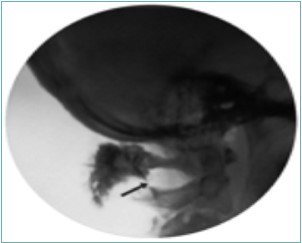

Figure 10.Lateral fluoroscopic image showing the final contrast spread; the arrow shows the outline of the greater occipital nerve at the level of the inferior oblique capitus muscle. Image Courtesy of Gabor Racz, MD

It is important to avoid positioning the needle in the area above C1 because of the rich venous plexus in that region. It is also important to monitor the flow of contrast, so that the medication does not migrate proximally into the subdural space.